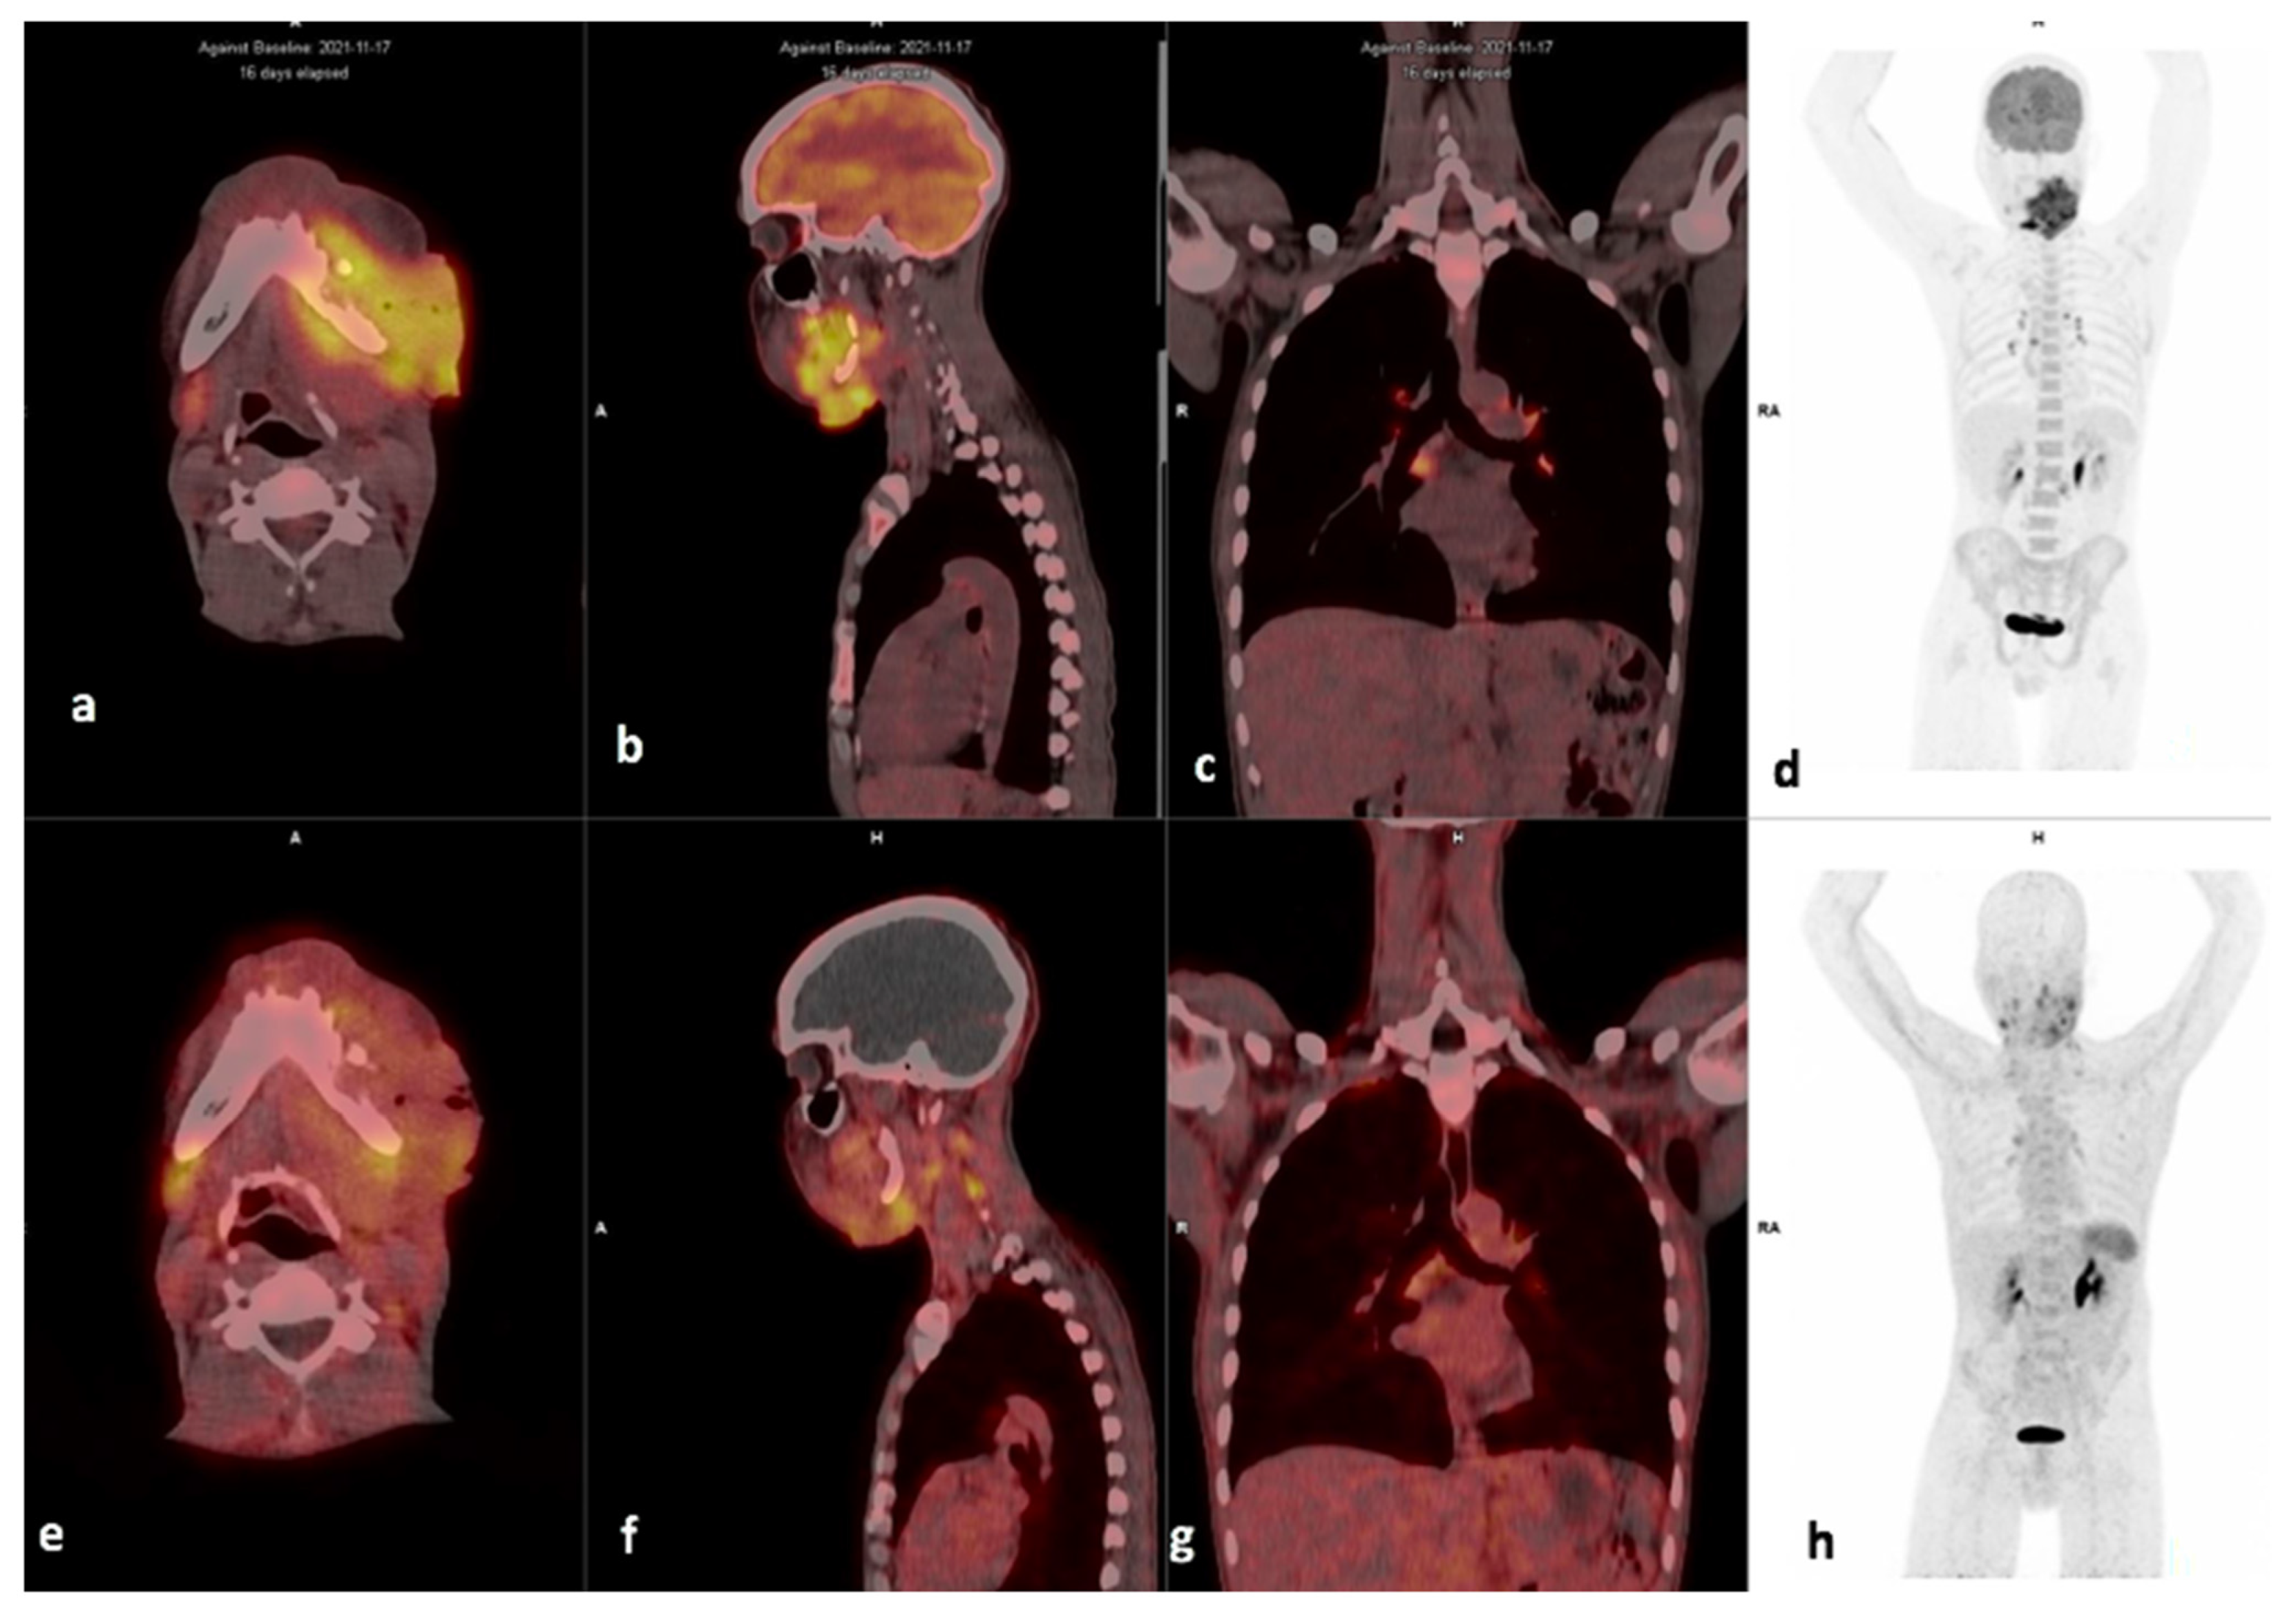

3.2. Comparison of FDG and 68Ga-Pentixafor

3.3. Visual Analysis

3.7. Metastasis